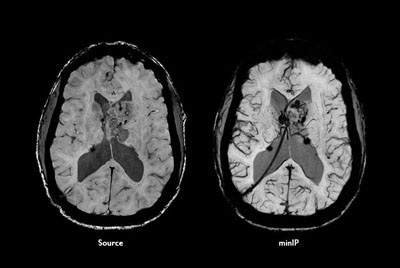

FLAIR* protocol for Multiple Sclerosis